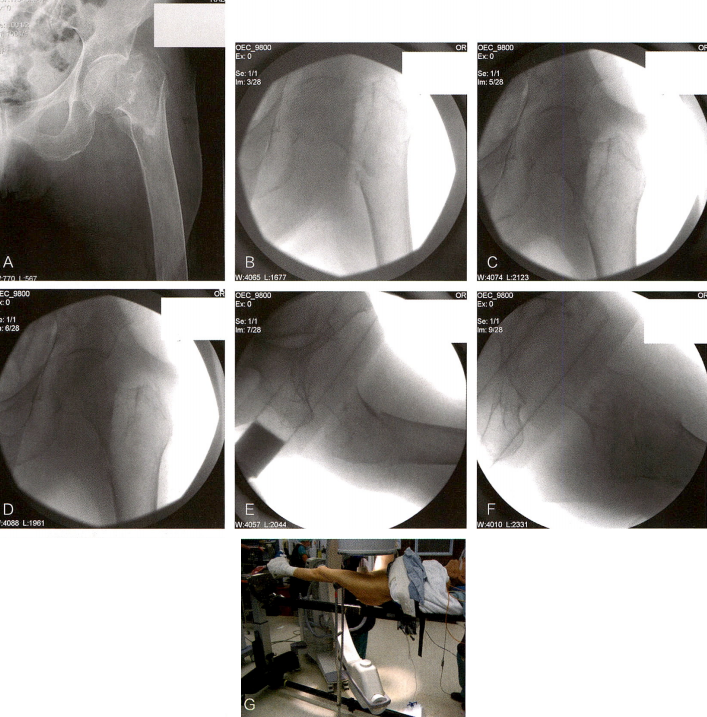

若尝试直接复位,应结合使用牵引、克氏针、复位钳和Schanz钉复位骨折(技术图5),并注意避免干扰后续的内固定置入。当获得预期复位后,依照内固定的操作规范,近端骨块内打入锁定螺钉的导针。使用股骨近端锁定钢板最关键的是要获得锁定螺钉的正确位置。细致的术前计划以及对各类型内固定设计的透彻理解是正确放置锁定螺钉及复位骨折的保证。近端骨块打入锁定螺钉前,应考虑到或纠正骨折在冠状面的成角畸形。

图片

技术图5 股骨近端锁定钢板固定。A、B.一例27岁女性31-A3型骨折患者的正侧位片。C.使用复位钳、克氏针、拉钩和股骨牵开器(作用于Schanz螺钉)达成术中复位。D、E.术中正、侧位片显示锁定钢板在位。F.术后1年右髋正位片显示下肢长度和力线维持良好,骨折已愈合。

注意,单独使用锁定螺钉无法在骨折区实现加压。若需加压,可以在打锁定螺钉时用复位钳夹紧骨折端。或者,某些内固定系统提供一种可以附加在非锁定螺钉头上的锁定帽,从而实现加压后的锁定固定。若闭合复位不成功,可以将钢板用作复位工具。钢板固定于近端骨块,注意不要留有内/外翻畸形。然后用复位钳将其与远端骨块对合复位,应注意复位后确保钢板与股骨的远端相贴合。应用带关节的张力装置、牵引或切开技术,有助于在将钢板固定于股骨干时,获得足够的长度恢复。